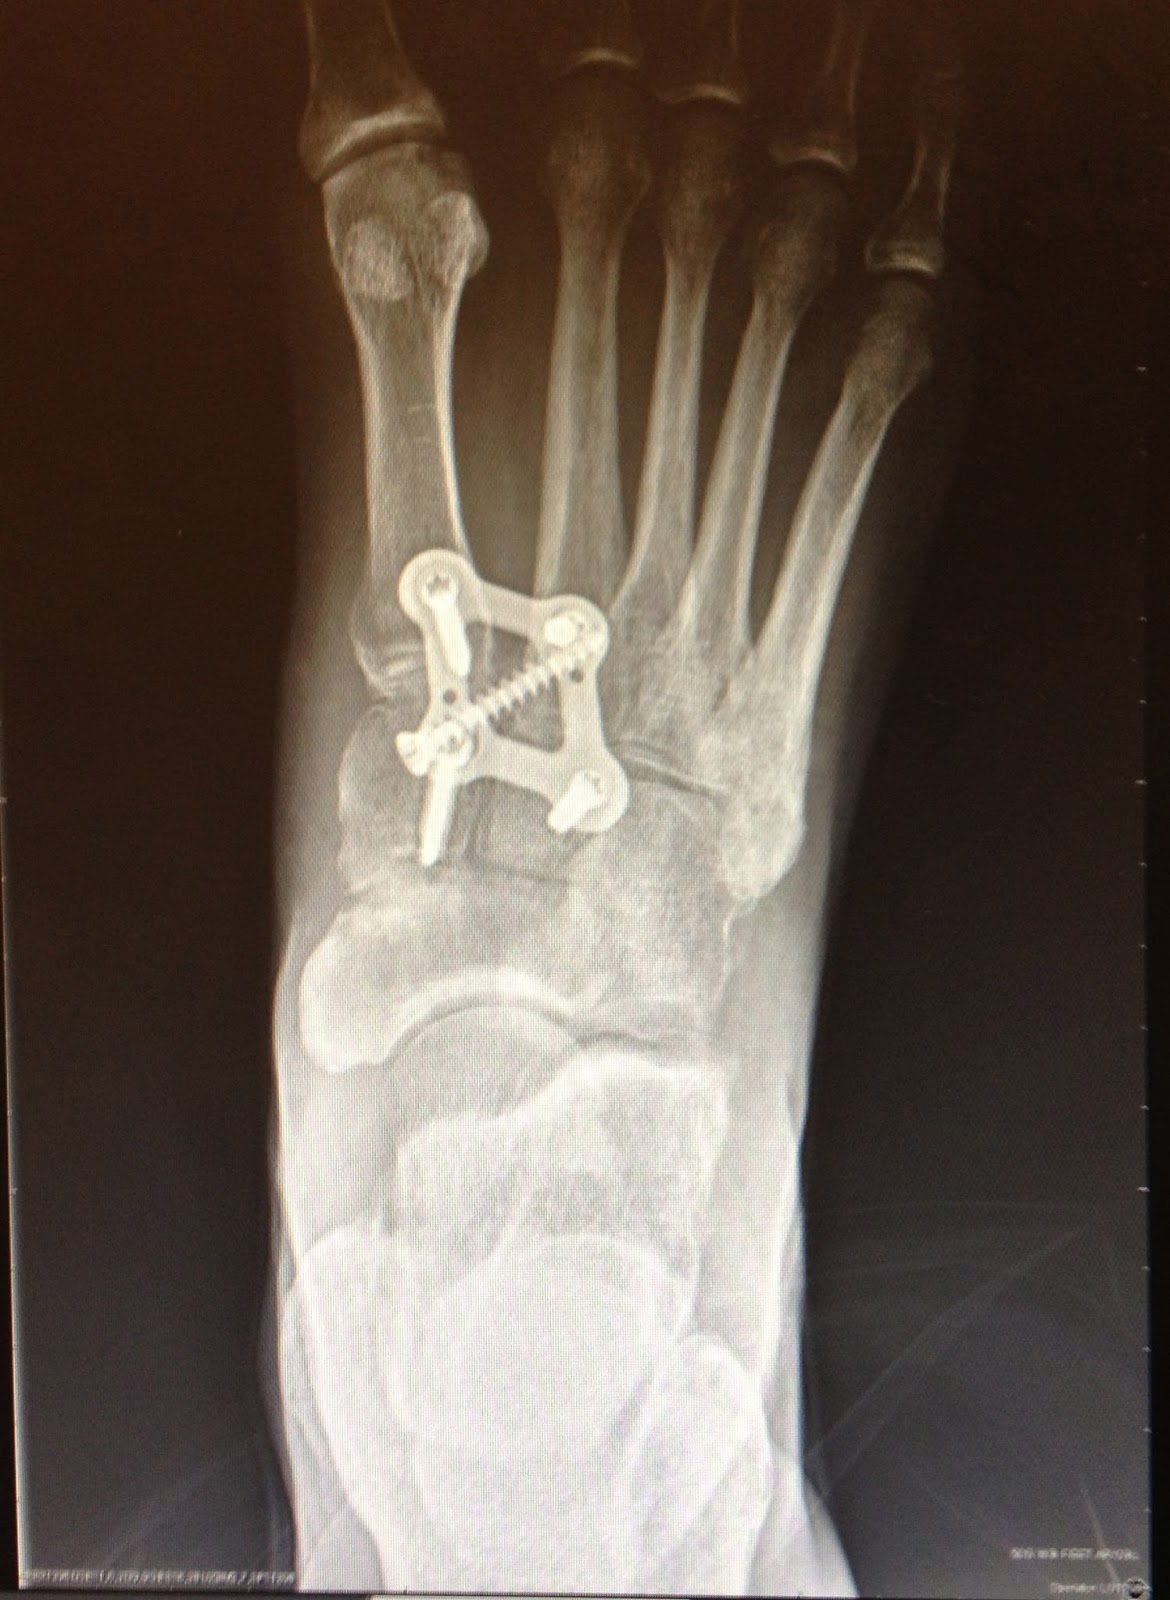

After LisFranc Surgery 22 weeks post lisfranc surgery

After LisFranc Surgery 12 weeks post lisfranc surgery Xrays How To Fix Lisfranc Fracture (center) a combination of plates and screws are sometimes required. (left) multiple screws can be used. Treatment for a lisfranc fracture will also depend on the severity of the injury. The lisfranc injury can vary widely, and the treatment plan will differ for each case. The forefoot is stuck in place and the force occurs through the athlete’s entire body. How To Fix Lisfranc Fracture.

After LisFranc Surgery 22 weeks post lisfranc surgery How To Fix Lisfranc Fracture The lisfranc injury can vary widely, and the treatment plan will differ for each case. (center) a combination of plates and screws are sometimes required. A lisfranc injury is a tarsometatarsal fracture dislocation characterized by traumatic disruption between the articulation of the medial. A mild lisfranc fracture can often be treated the same way as a. The forefoot is stuck. How To Fix Lisfranc Fracture.